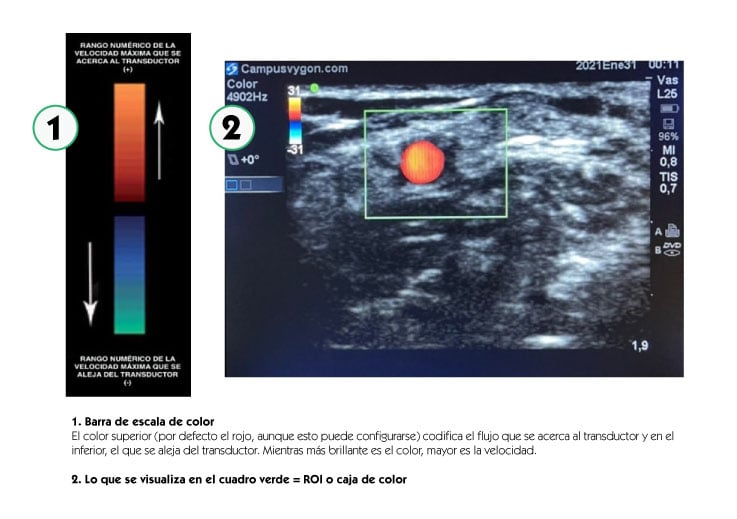

Mediante la aplicación del modo doppler color, se codifica la velocidad media del flujo estudiado, asignándole un color que va a estar determinado en relación con el sentido del flujo, de acuerdo con una determinada escala, superponiéndola a la imagen en Modo B (bidimensional o escala en blanco y negro). El ROI (Region Of Interest: Zona De Interés) o caja de color, determinará la zona de muestreo.

Manteniendo la exploración en modo B, activamos el modo doppler color y situamos el ROI o cuadro de color en la estructura que queramos estudiar, asignando un tamaño adecuado al mismo.

Posteriormente, angulamos el transductor entre 30 a 60º o bien hacia la parte distal del cuerpo (hacia la mano), o hacia la parte proximal (hacia la cabeza). Por último, volvemos a activar el modo doppler color para que comience el análisis, obteniendo una tonalidad roja al identificar el flujo que fluye hacia el transductor o azul si éste, se aleja.

En el estudio de las extremidades, si basculamos la sonda de tal manera que los ultrasonidos se dirigen hacia la cabeza del paciente, los vasos que veamos en color rojo serán arterias y los que veamos en color azul serán venas. En la tabla adjunta se muestran las diferentes combinaciones con las que estudiar el capital vascular del paciente con modo doppler color en plano transversal.